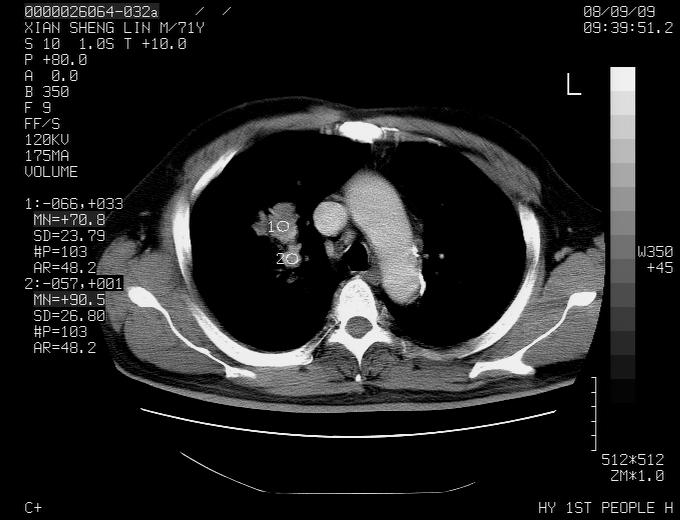

标题: CT15869:男性,71岁,因咳嗽而就诊,请讨论右上肺病变性质 [打印本页]

患者,男性,71岁,因咳嗽而就诊,

典型的右肺中心性肺癌并纵隔淋巴结转移

右肺中心性肺癌并纵隔淋巴结转移可能性大!

考虑右肺中心性肺癌并右肺门及纵隔淋巴结转移。

1,右肺中心型ca,气管隆突旁淋巴结转移。